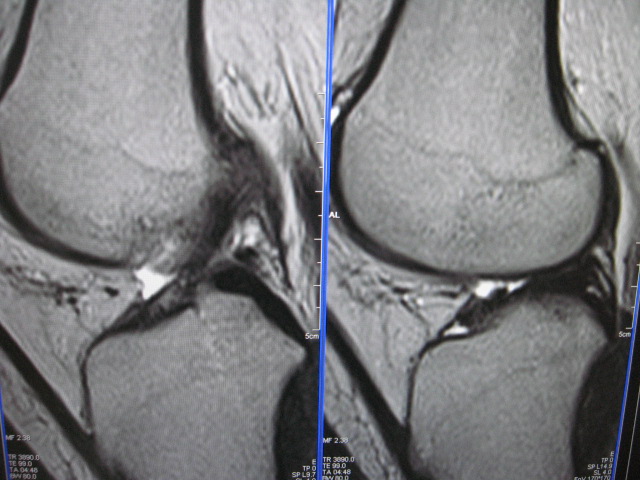

以下是引用克山在2007-10-21 9:57:00的发言:[br]符合股骨外侧髁剥脱性骨软骨炎。创伤是其主要原因,病理上为软骨下骨质局限性缺血性坏死,好发股骨内外侧髁,mr表现为软骨下局限性长t1长t2信号,有时t2像周围可见条状高信号。

以下是引用453506471在2007-10-19 22:23:00的发言:[br]剥脱性骨软骨炎